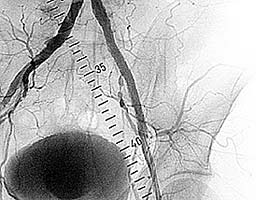

Пациент с жалобами на перемежающуюся хромоту,

боли возникают после ходьбы 20м.

На ангиограмме - стенозы наружной

подвздошной и общей бедренной артерий (рис.4).

В место стенозов установлен

саморасправляющийся стент (рис.5).

Стенозы устранены (рис.6).

| Рис.5 |